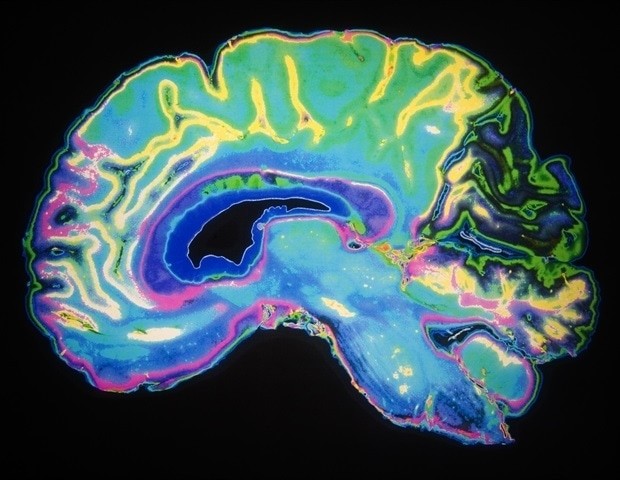

A new finding from researchers at Georgetown University Medical Center shows that the learning process of associating cues with rewards can be altered by increased or decreased activity of a specific protein in the brain. Knowing when to respond positively to cues that result in beneficial outcomes or rewards vs. ignoring cues that result in bad habits, such as smoking addiction, is an essential part of learned behaviors.

Our ability to link certain cues or stimuli with positive or rewarding experiences is a basic brain process, and it is disrupted in many conditions such as addiction, depression, and schizophrenia. For example, drug abuse can cause changes in the KCC2 protein that is crucial for normal learning. By interfering with this mechanism, addictive substances can hijack the learning process."

The investigators found that changes in the learning process can happen because of changes in KCC2. In what is an inverse relationship, diminished KCC2 levels can cause increased dopamine neuron firing, which in turn leads to new reward associations being formed. Dopamine neurons are specialized nerve cells that produce and release the neurotransmitter dopamine that is involved in reward, motivation, and motor control.